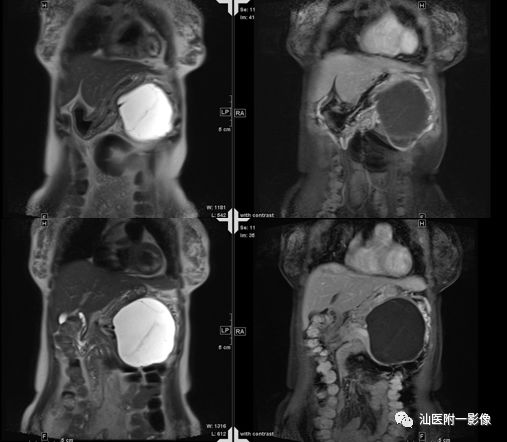

·男,15岁,上腹痛3天,加重半天

·3天前无明显诱因出现上腹痛,呈持续性痛。半天前症状突然加重。查体:全腹部腹肌紧张,左上腹部压痛及反跳痛明显。

·外院B超:左上腹囊性包块,考虑胰腺假性囊肿,未排其它

病例二 胰腺假性囊肿